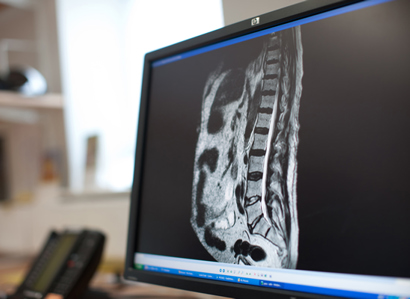

MSCC is rare; between 5 and 10% of cancer patients develop spinal cord compression.

Read What is MSCC? Article